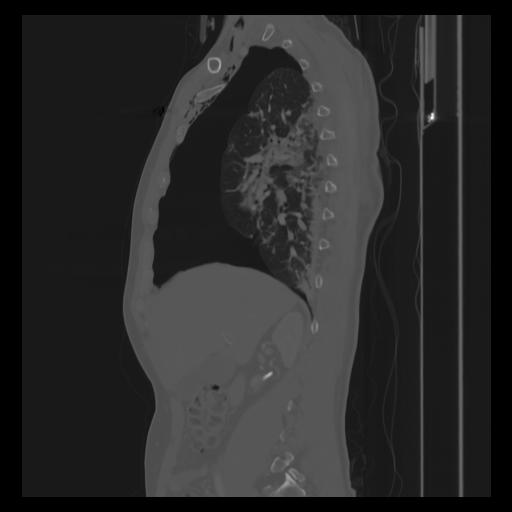

30 CUERPO,CE,Sagittal,3.000,CUERPO,Sagittal,